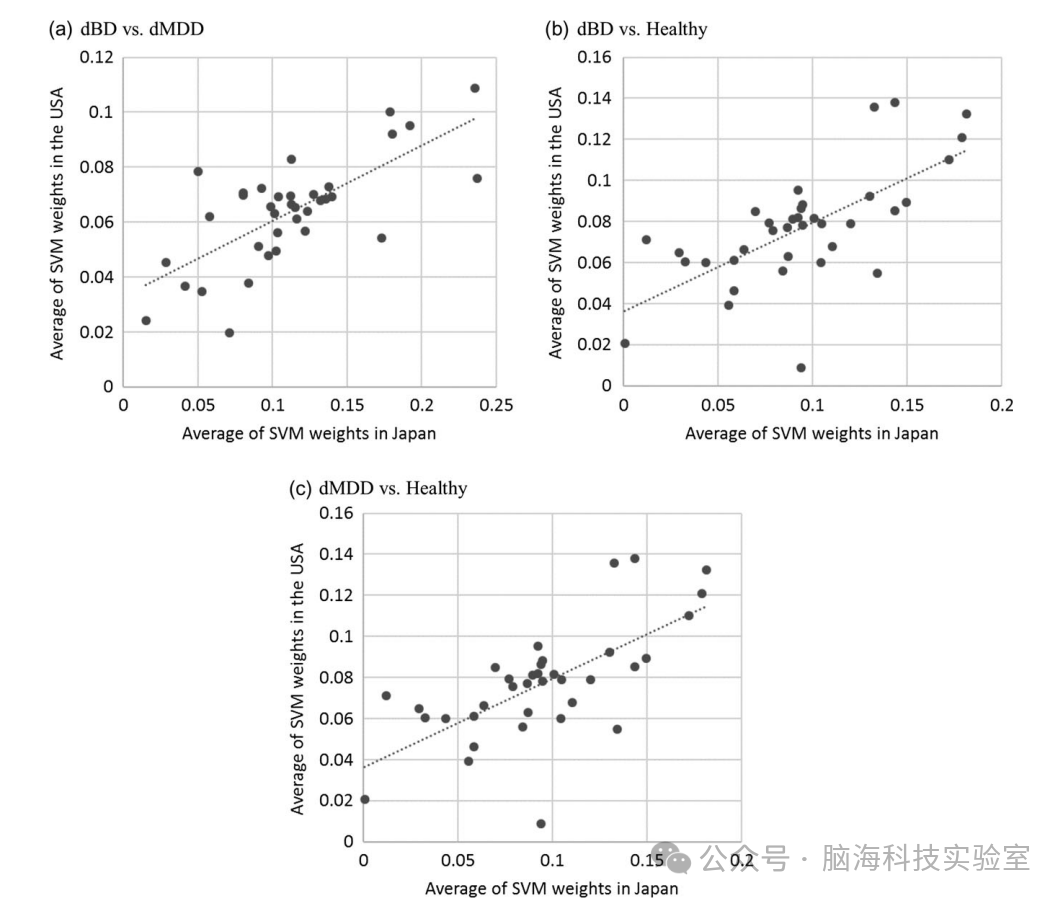

为了探究美国样本分类能力较低的原因,研究团队对美国样本进行了与日本样本相同的交叉验证。结果显示,美国样本的分类准确率低于日本样本。尽管如此,美国样本和日本样本在区域SVM权重之间的相关性显著(r=0.72,P<0.001;r=0.68,P<0.001;r=0.73,P<0.001),表明两个样本在区域SVM权重的排名上表现出相似的趋势,且在所有诊断中,双侧上额回和中额回的SVM权重最大。

图2:用于跨诊断分类的支持向量机(SVM)权重的区域散点图及其平均值

第四,研究使用训练数据对SVM分析的最优参数C进行了10折交叉验证,使用了5个候选参数。研究可能通过使用网格搜索图方法找到更优的参数。使用的5个典型参数候选在本研究中经过探索性测试后被确认为适当(数据未显示)。研究使用PCA对每个区域进行特征提取,保留了90%的方差,这没有通过交叉验证进行优化。首先通过保留95%的方差进行这种特征提取分析,结果与保留90%方差的原始分析略有不同(数据未显示)。因此,尽管更好的参数优化可能会提高SVM的分类性能,但研究目前的结果仍然是有效的。第五,研究发现美国样本的SVM交叉验证显示出非常低的敏感性(dBD与健康为0.18,dMDD与健康为0.13)。这可能是由于患者与健康受试者之间的样本量严重不平衡(36例dBD、43例dMDD与132例健康受试者)。未来需要在美国样本中进行三组诊断数量相当的研究,以进一步验证结果。最后,平均SVM权重的结果表明,日本和美国的结果之间显示出相似的分布(图4)。似乎较大的权重简单地出现在较大的区域中,但事实可能并非如此简单。由于SVM分析使用了从VBM分析中获得的体素信号强度,一个区域中的较大权重意味着更大的平均体素信号和更多的体素数量。例如,它可能表明左右两侧的ROI(应该包含相似数量的体素)位于不同的位置(补充表5)。因此,尽管较大的区域倾向于显示出较大的权重,但在解释图4的结果时,应考虑每个体素的信号强度。

图4:第一和第二队列中支持向量机权重平均值之间的比较散点图